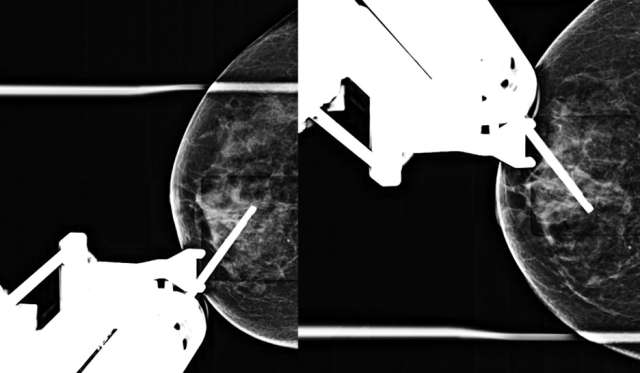

- Technologist repeats stereotactic pair (+/- 15 degrees) and radiologist confirms accurate trajectory on the postfire images (Figure 4).

Figure 4. Postfire stereotactic pair of CC images taken +/- 15 degrees oblique.